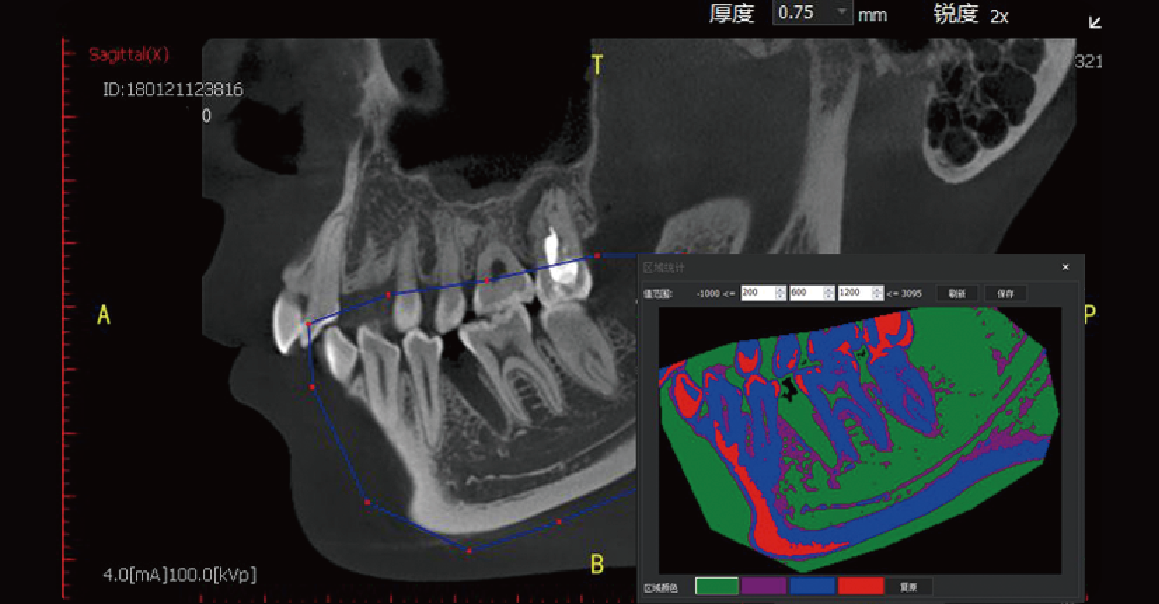

Regional Statistics

Used to evaluate bone mineral density in a selected area.